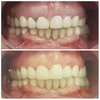

Zirkonyum uygulamalar

Porselen uygulamaları

Laminate veneer